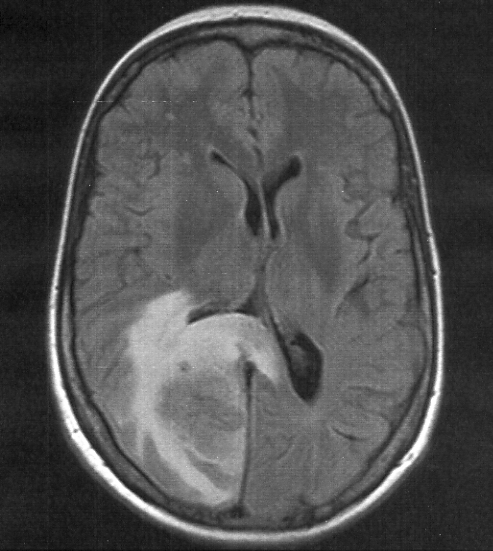

A Rare Case of Mannitol-Induced Anaphylaxis During Treatment of Cerebral Edema

A Case Report | 22 Oct 2025